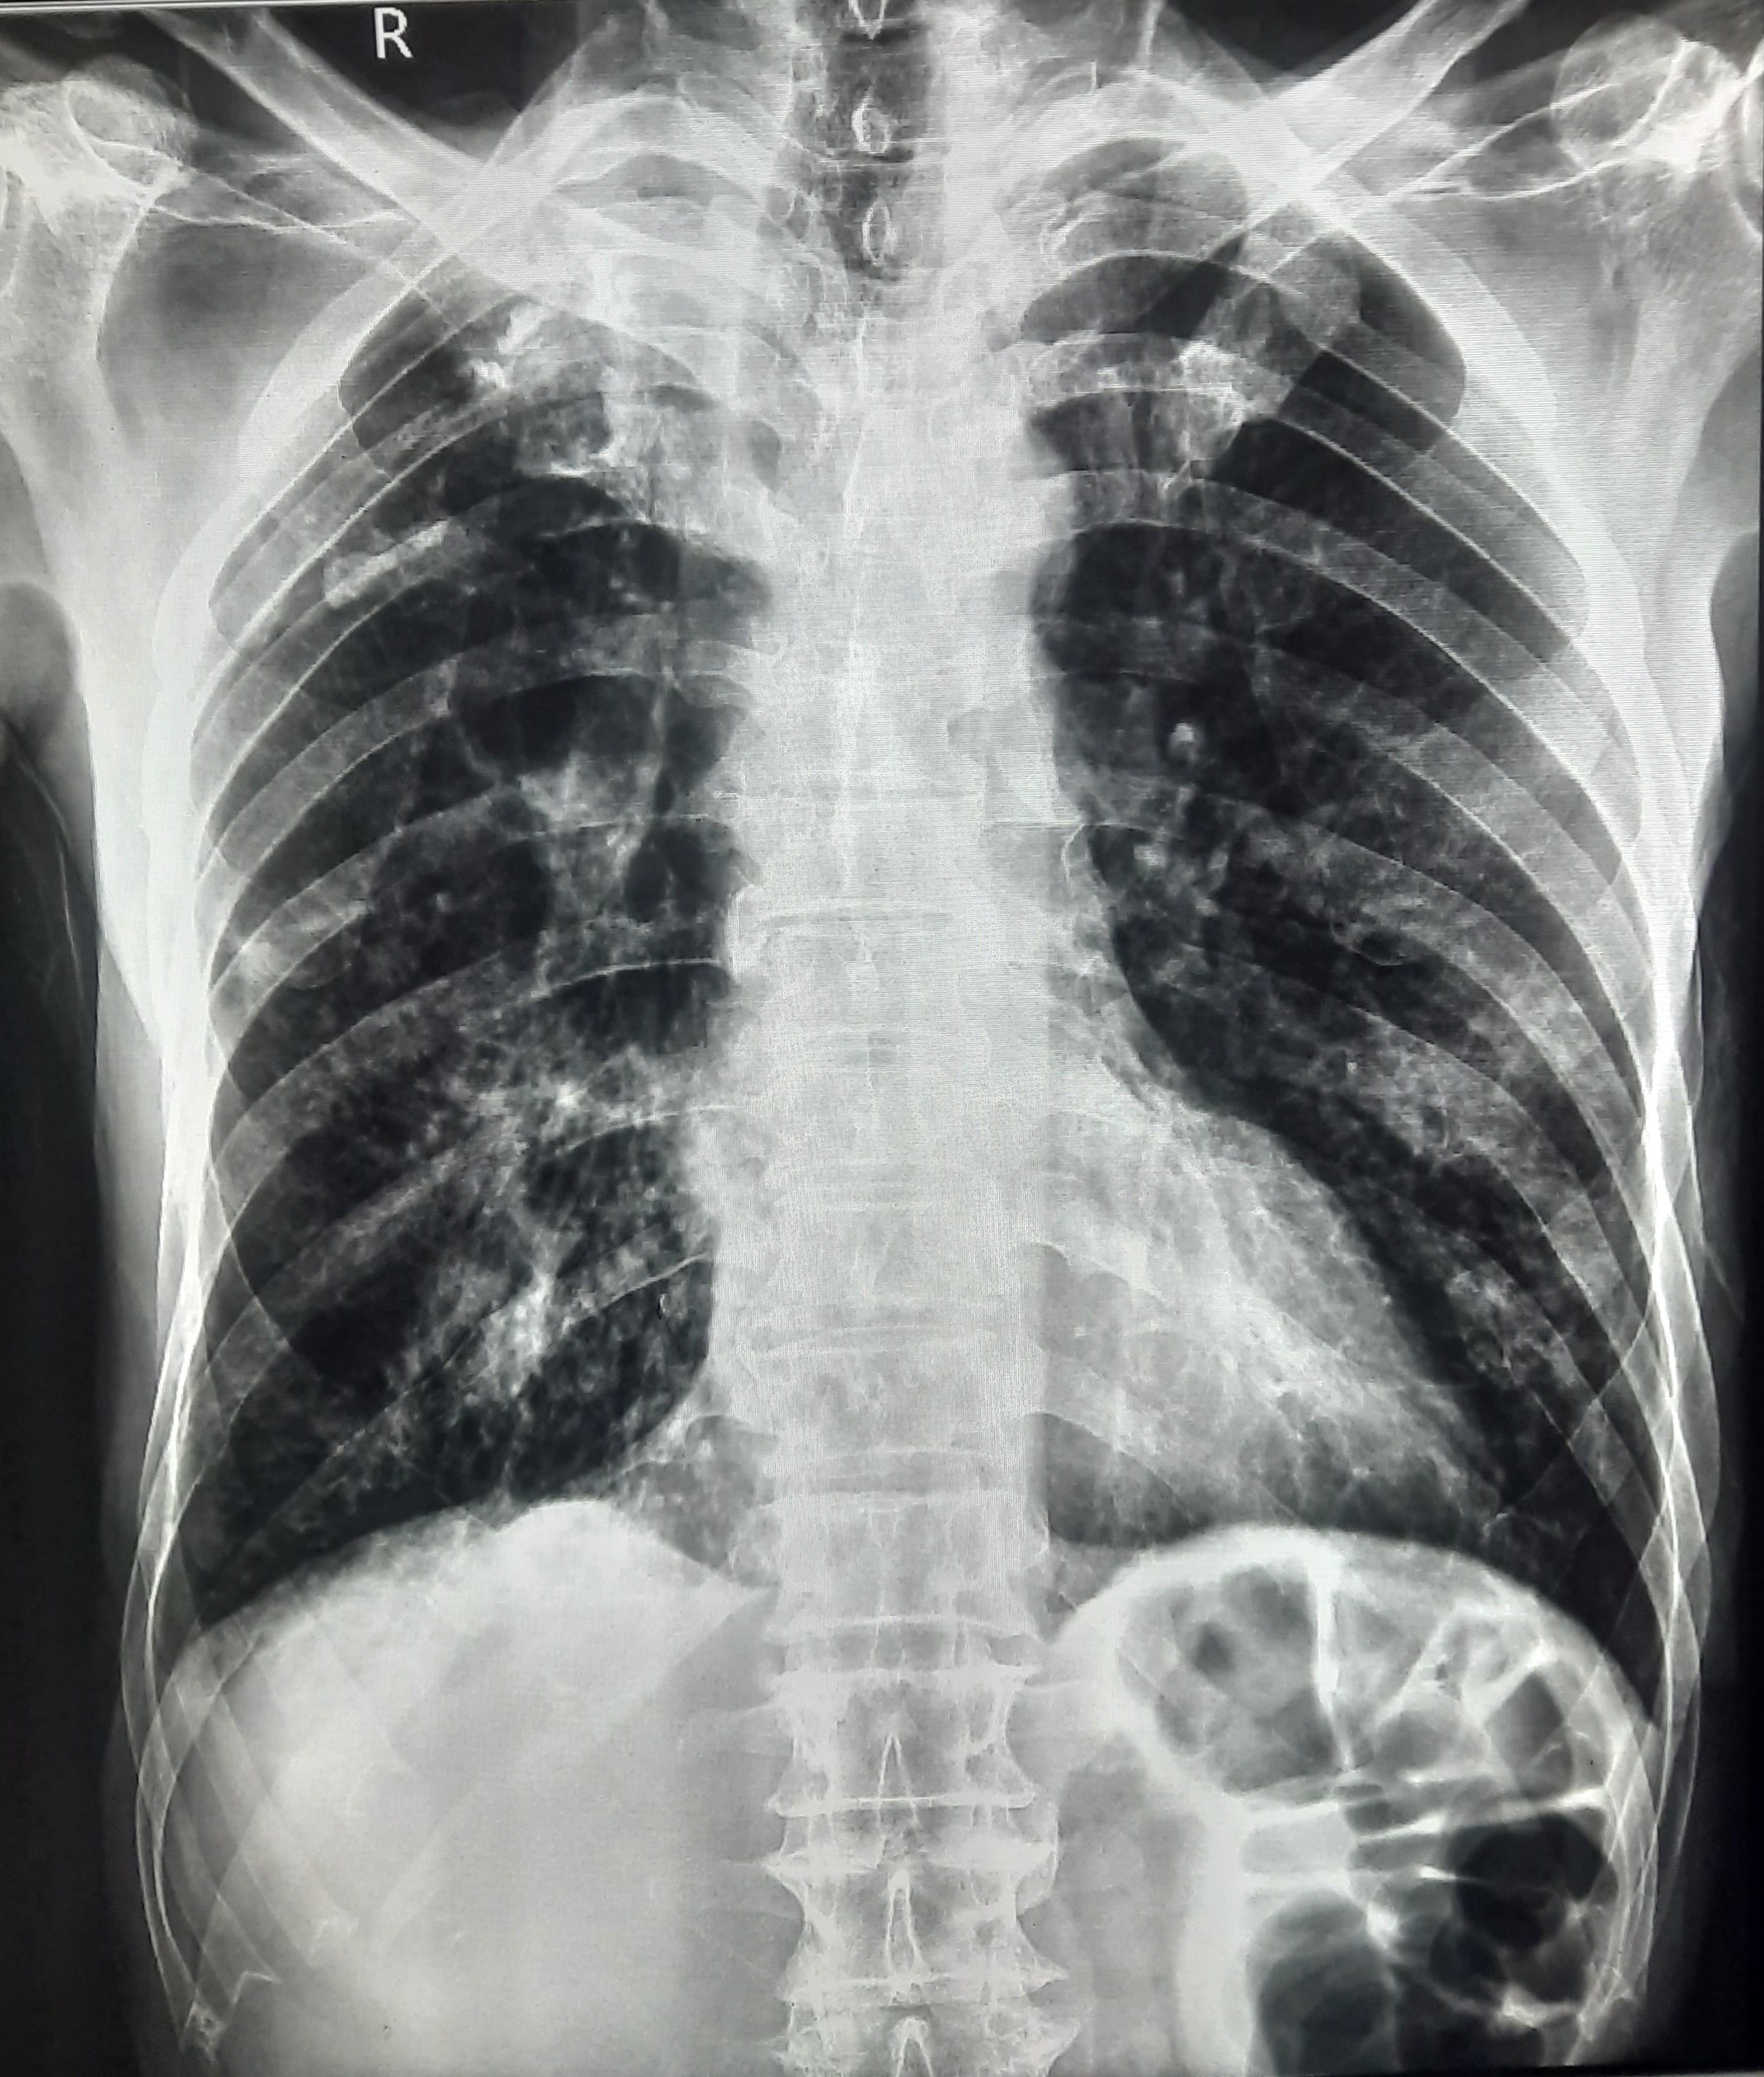

| 60 | IGGMC, Nagpur, Nagpur | P2 | 29-4412 | Ritesh Uikey | Consent taken on Paper | 30 Yrs. |

Provisional Diag : Pulmonary Tuberculosis

Final Diag : Pulmonary Tuberculosis |

TB Case (Confirmed) | Bilateral Lung Infiltration Present & Right Upper Zone Cavity Present | Abnormality visible on x-ray |